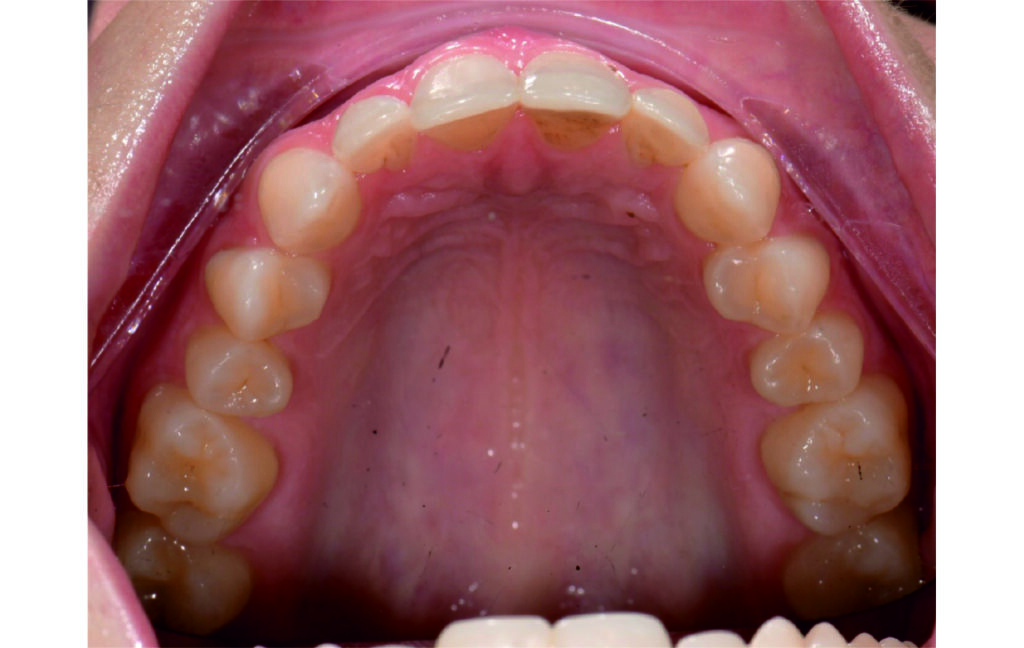

Angle Class II 2mm on the right, Angle Class II 2mm on the left, light mandibular asymmetry to the right, lower central line 1mm to the right, upper central line 1,5mm to the left, 1mm overjet and overbite. Sagittal asymmetry of upper dental arch. Light crowding upper and lower frontal segments, severe attrition of posterior teeth, night bruxism. Normal sagittal position of both jaws, high angle case, steep mandibular ramus,excessive lower facial height, open bite tendency.

A 1.5 mm deviation of the upper dental midline to the patient’s left was noted, along with a slight mandibular midline shift to the right, likely due to asymmetrical mandibular growth observed in the facial structure. Severe mesial rotations of teeth 16 and 26 were evident in the initial records. As derotation of 16, 26, 17, and 27 progressed up to aligner 16, the premolars in segments I and II moved distally, resulting in a bilateral Class I relationship, as intended in the initial treatment plan.

An infrazygomatic crest (IZC) screw with force applied between the upper premolars produces a clockwise rotation of the maxillary occlusal plane. This movement aids in closing the anterior open bite and improves upper incisor display. IZC screws with elastics also enable planned intrusion of the upper molars by 1 mm. Because mandibular derotation after upper posterior correction is difficult to predict, anterior distalization and midline correction were performed in the later stages of treatment.